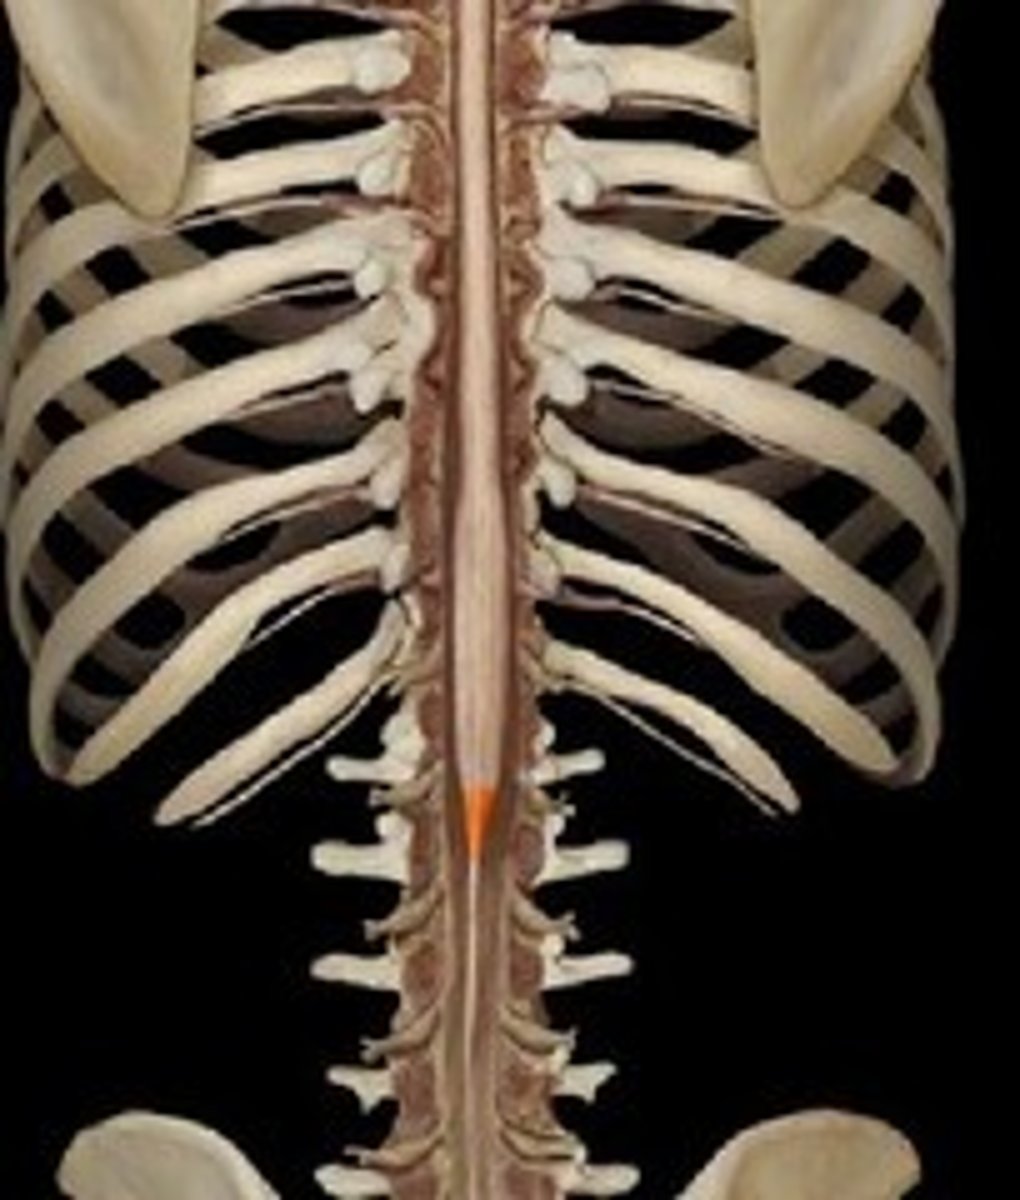

conus medullaris

cauda equina